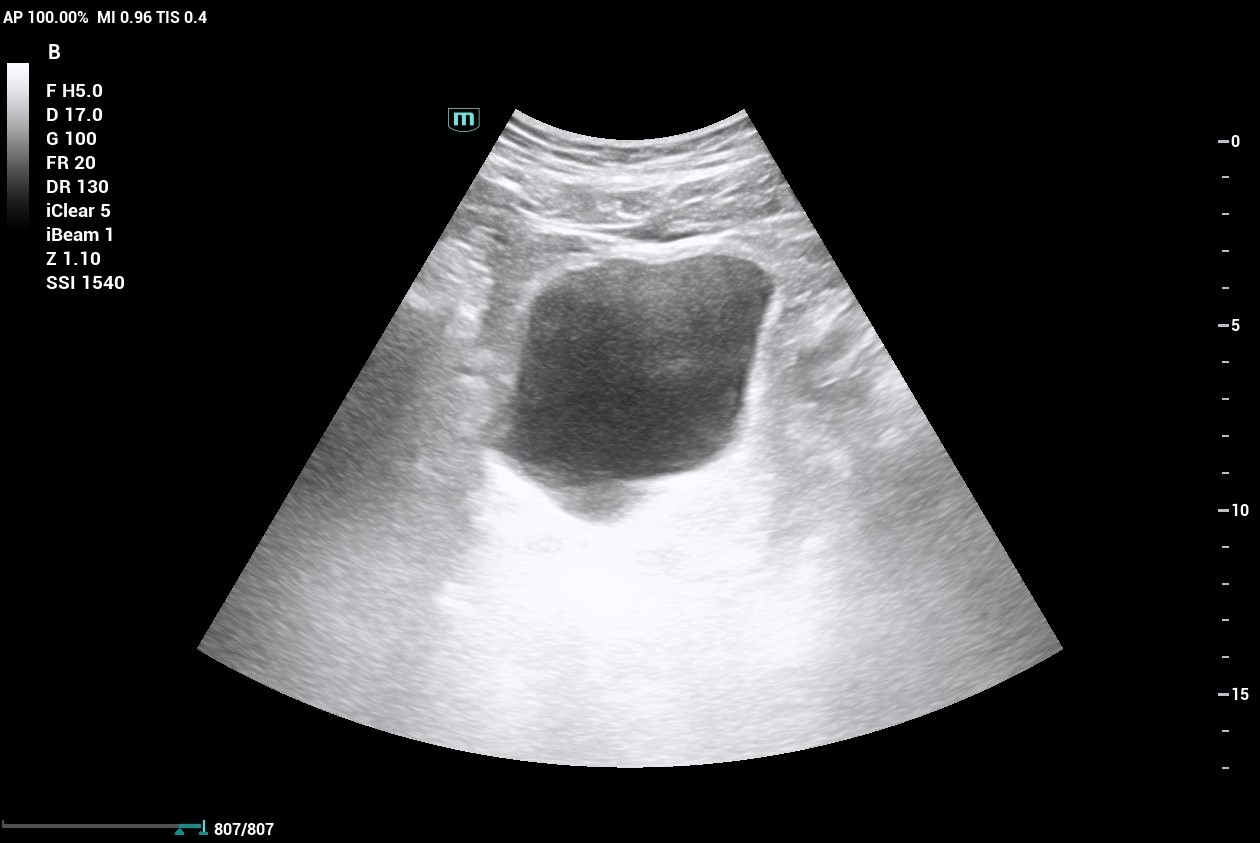

ULTRAHANG DIAGNOSZTIKA

Időpont egyeztetés a +36 30 9022 154 vagy a +36 34 473-030 telefonszámon.